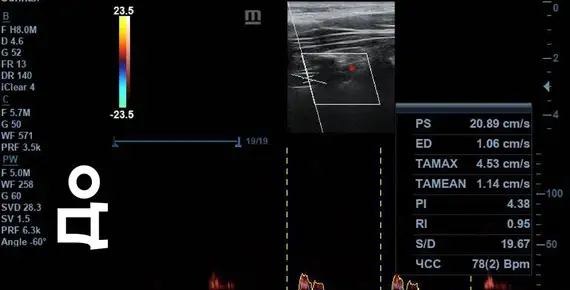

Скорость кровотока «ДО»